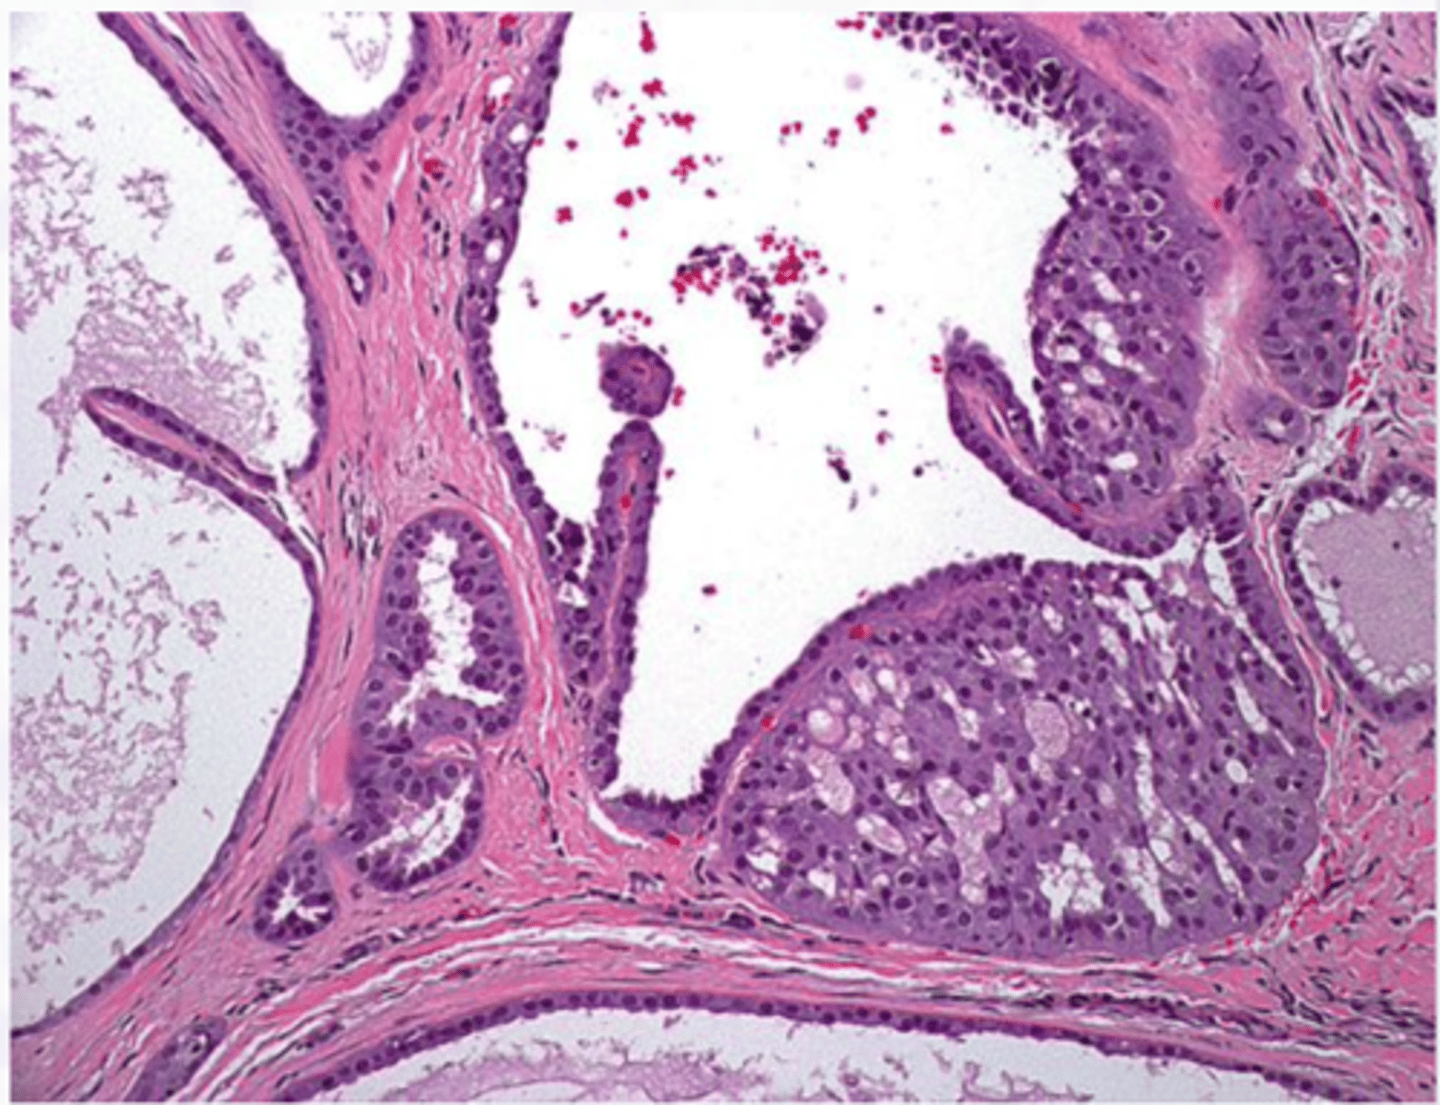

Ductal Papilloma

Benign Salivary Gland Tumors:

Exophytic and Papillary, Minor salivary glands

Inverted type

▫ lower lip and MD vestibule

▫ indentation

• Papillary projections

• Inflammation

• Intraductal

▫ inside a duct